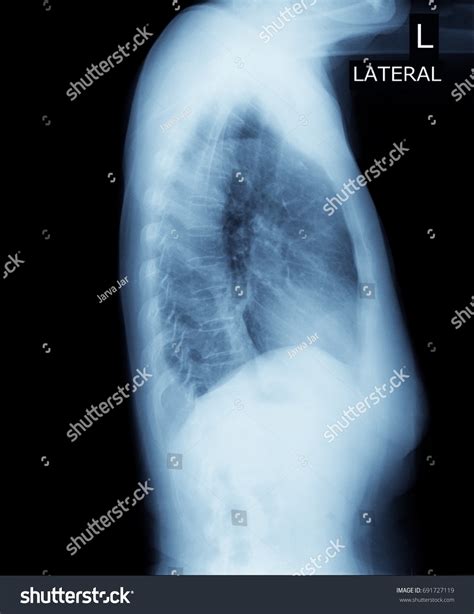

• Radiographic Imaging: It is frequently used in chest X-rays to detect small amounts of pleural effusion or pneumothorax that might not be visible in an upright or supine position.

When performing imaging in the Right Lateral Decubitus position, technicians must be precise with beam angulation and patient orientation. If the goal is to detect a pleural effusion, the patient is placed so that the side being examined is the "down" side. This allows the fluid to gravitate to the dependent portion of the thoracic cavity, where it is more easily identified against the chest wall. Conversely, if searching for free intraperitoneal air (pneumoperitoneum), the patient is often placed so that the potential air space is at the highest point.